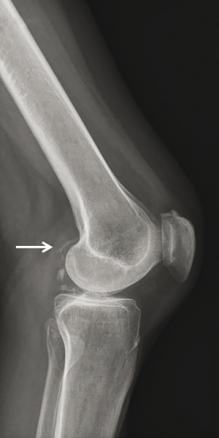

© Gérard Chalès, Pascal Guggenbuhl (La Revue du Praticien) Radiographie de genou de profil. Liseré de chondrocalcinose bordant le cartilage. Tiré de : Guggenbuhl P, Coiffier G, Albert JD, Chalès G. Dossier. Arthropathies microcristallines. Rev Prat 2015;65(5):665-82.